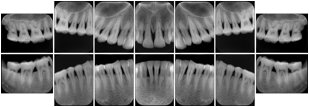

OO.1.2 Ophthalmology

1. A patient in rural Canada visits a general ophthalmologist and is found to have diabetic macular edema. The general ophthalmologist would like to discuss the case with a retina specialist before performing laser surgery. A fluorescein angiogram is done with multiple retinal images taken in a timed series after an intravenous injection. The images along with a Structured Display are shared via a Health Information Exchange with a retina specialist in Calgary, who opens them using his Ophthalmology EMR software and consults via phone with the general ophthalmologist. Both physicians view the images in the same layout so the retina specialist can provide accurate guidance for treating the patient.

2. A patient in rural Iowa visits his primary care physician for management of diabetes. Three non-mydriatic (patient's eyes are not dilated) photographs are taken of the back of each eye, and forwarded electronically along with a Structured Display to an ophthalmologist in Iowa City. The ophthalmologist reads the photos in an agreed upon layout so there is no mistake about what portion of which eye is being viewed. The ophthalmologist is able to tell the primary care physician that his patient does not need to come to Iowa City for face to face ophthalmologic care, but that there is a particular view of the left eye that should be photographed again in 6 months.

Ophthalmic Retinal Study Structured Display

Figure OO-3. Ophthalmic Retinal Study Structured Display

3. A patient in rural Minnesota experiences sudden vision loss and goes to a general ophthalmologist, who acquires OCT images and forwards them electronically along with a Structured Display to a retina specialist six travel hours away. The retina specialist is able to view the images in the standard layout that he is comfortable with, and to confirm that the patient has a choroidal neovascular membrane. He determines that is would be worthwhile for the patient to travel for treatment.

OCT Retinal Study with Cross Section and Navigation Structured Display

Figure OO-4. OCT Retinal Study with Cross Section and Navigation Structured Display